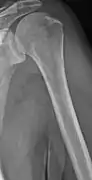

X-ray of the forearm, with lytic lesions

Multiple myeloma in the upper arm

The diagnostic examination of a person with suspected multiple myeloma typically includes a skeletal survey. This is a series of X-rays of the skull, axial skeleton, and proximal long bones. Myeloma activity sometimes appears as "lytic lesions" (with local disappearance of normal bone due to resorption). And on the skull X-ray as "punched-out lesions" (pepper-pot skull). Lesions may also be sclerotic, which is seen as radiodense.[47] Overall, the radiodensity of myeloma is between −30 and 120 Hounsfield units (HU).[48] Magnetic resonance imaging is more sensitive than simple X-rays in the detection of lytic lesions, and may supersede a skeletal survey, especially when vertebral disease is suspected. Occasionally, a CT scan is performed to measure the size of soft-tissue plasmacytomas. Bone scans are typically not of any additional value in the workup of people with myeloma (no new bone formation; lytic lesions not well visualized on bone scan).